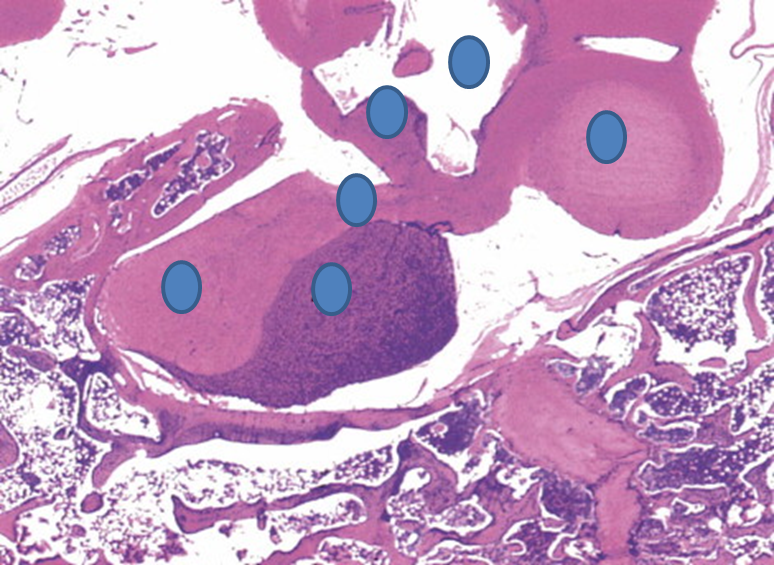

Where are these tissue samples taken from?

Parathyroid. Recognize from the presence of adipocytes.

Identify the structures indicated.

Light - Posterior Lobe, Neurohypophysis

Dark - Anterior Lobe, Adenohypophysis